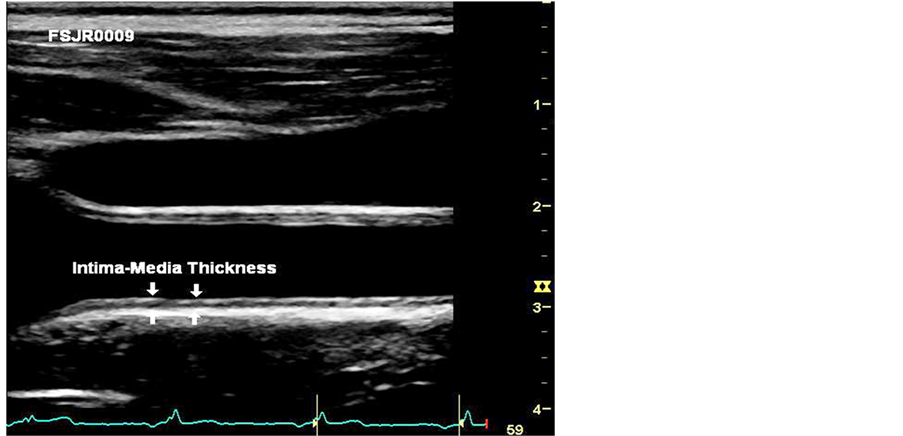

Bilateral resting blood pressure was measured in the seated upright position using a standard medical sphygmomanometer and an appropriate sized cuff. Fasting blood glucose levels were obtained with a standard TRUE result TM glucometer (Nipro Diagnostics Inc., Fort Lauderdale, FL, USA). Fasting lipid levels, including cholesterol, triglyceride, high density lipoprotein and low density lipoprotein, were obtained using a CardioChekP. Aanalyzer TM (Polymer Technology Systems Inc., Indianapolis, IN, USA).With the subject supine, B-mode images of their bilateral common carotid artery (CCA) and their bilateral carotid bulb were obtained with a GE Vivid ETM ultrasound machine fitted with an 8L-RS high frequency linear array transducer (GE Healthcare, Waukesha, WI, USA). Transverse and longitudinal images were obtained and evaluated onsite for the presence of clinically significant plaque formation. Longitudinal images of the carotid artery were recorded in 3 - 5 heart beat cine loops with optimal visualization of the near and far walls of the distal 1 cm of the CCA and the proximal carotid bulb. Images were recorded in the longitudinal plane from three different optimal acquisition angles of incidence showing near and far wall double lines indicating true perpendicular scanning planes by the same sonographer experienced in obtaining images for CIMT measurements (Figure 1), as recommended by the American Society of Echocardiography (Morrisville, North Carolina, USA) and the Society of Vascular Medicine (Deerfield, Illinois, USA) [21] .

Figure 1 shows an example ultrasound B-mode capture to detail optimal intima-media thickness of a carotid artery.

Figure 1. Carotid intima-media thickness measurement at optimal depth, on the R-wave.